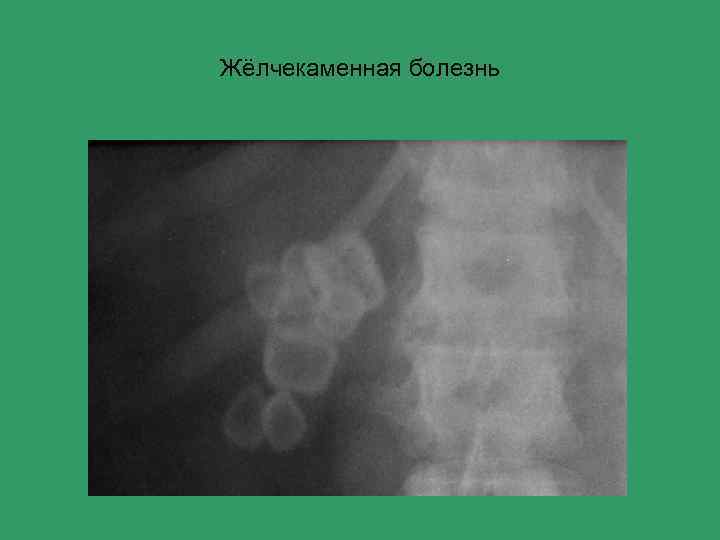

Жёлчекаменная болезнь